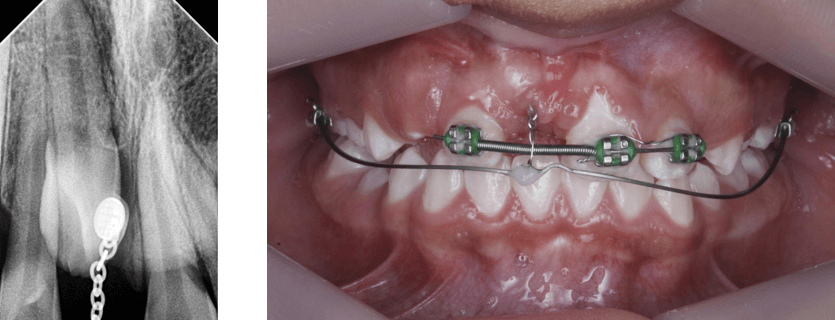

Posterior a la cirugía se realizó una radiografía panorámica y periapical con técnica de bisectriz como método de control para el tratamiento (Fig 14 y 15 ) y la activación del botón de tracción con el arco 16x22 niti superior (Fig 16).

Fig 14 y 15. Rx periapical N1 con botón y cadeneta y Rx panorámica

En el siguiente mes se utilizó la técnica de tracción con arco segmentado, donde se utilizaron el arco 0.018 niti superior sujeto a los incisivos superiores 1.2, 2.2 y 2.1 junto con un resorte de espigas cerradas para mantener el espacio entre el 1.2 y 2.1 y el arco de TMA 17 x 25 colocado en los tubos 16 y 26 respectivamente. Se realiza la activación con 100 gramos de fuerza. (Fig 17)

Fig 17. Fotografía de arco segmentado 0.018 para tracción de incisivo central 1.1

En el siguiente mes se realizó la toma de la radiografía periapical N2 (Fig 18) para verificación de la distancia que ha recorrido el incisivo central, se continúa con el uso del arco segmentado 17 x 25 TMA cortando las argollas sobrantes de la cadeneta y calibrando la fuerza a 100gr para continuar con el proceso. (Fig 20)

Fig 18. Rx periapical N2 - Fig 20. Fotografía control de arco segmentado